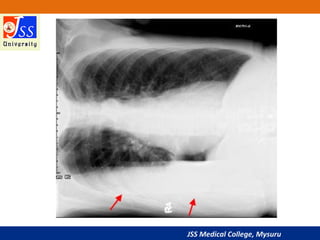

Lateral Decubitus Position

patient’s left side down against the film)

• Often useful in revealing a pleural effusion that cannot be

easily observed in an upright view, since the effusion will

collect in the dependent position

•Supraclavicular fossae

(enlarged nodes)

•Lateral chest wall

(surgical emphysema)

•Under diaphragm

(pneumoperitoneum)

Soft Tissues